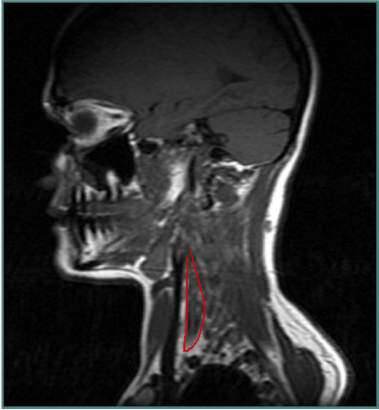

ACCURACY OF LOCALIZATION - SCALENES

ACCURACY OF LOCALIZATION LEVATOR SCAPULAE

LOCALIZATION OF MUSCLES IN DEEPER LAYERS

- Muscles deep

- Not easily identified by surface landmarks

- Not palpable on examination